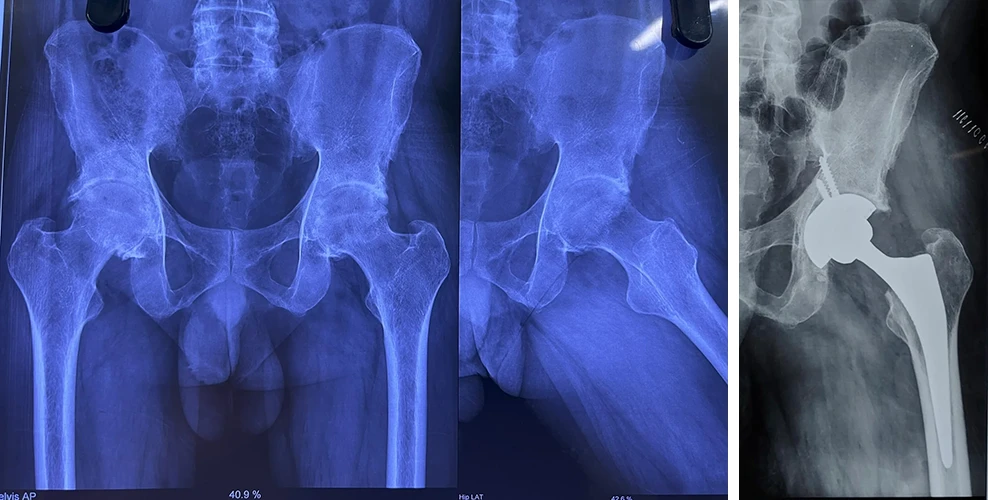

Total Hip Replacement

Are your hips causing you constant discomfort? If you're tired of living with hip pain, Dr. Prasun Sanyal is your best solution.